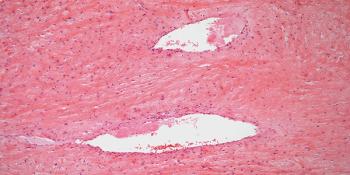

A 34-year-old woman presents with an increase in uterine bleeding. A biopsy is performed during a gynecologic examination. What is your diagnosis?